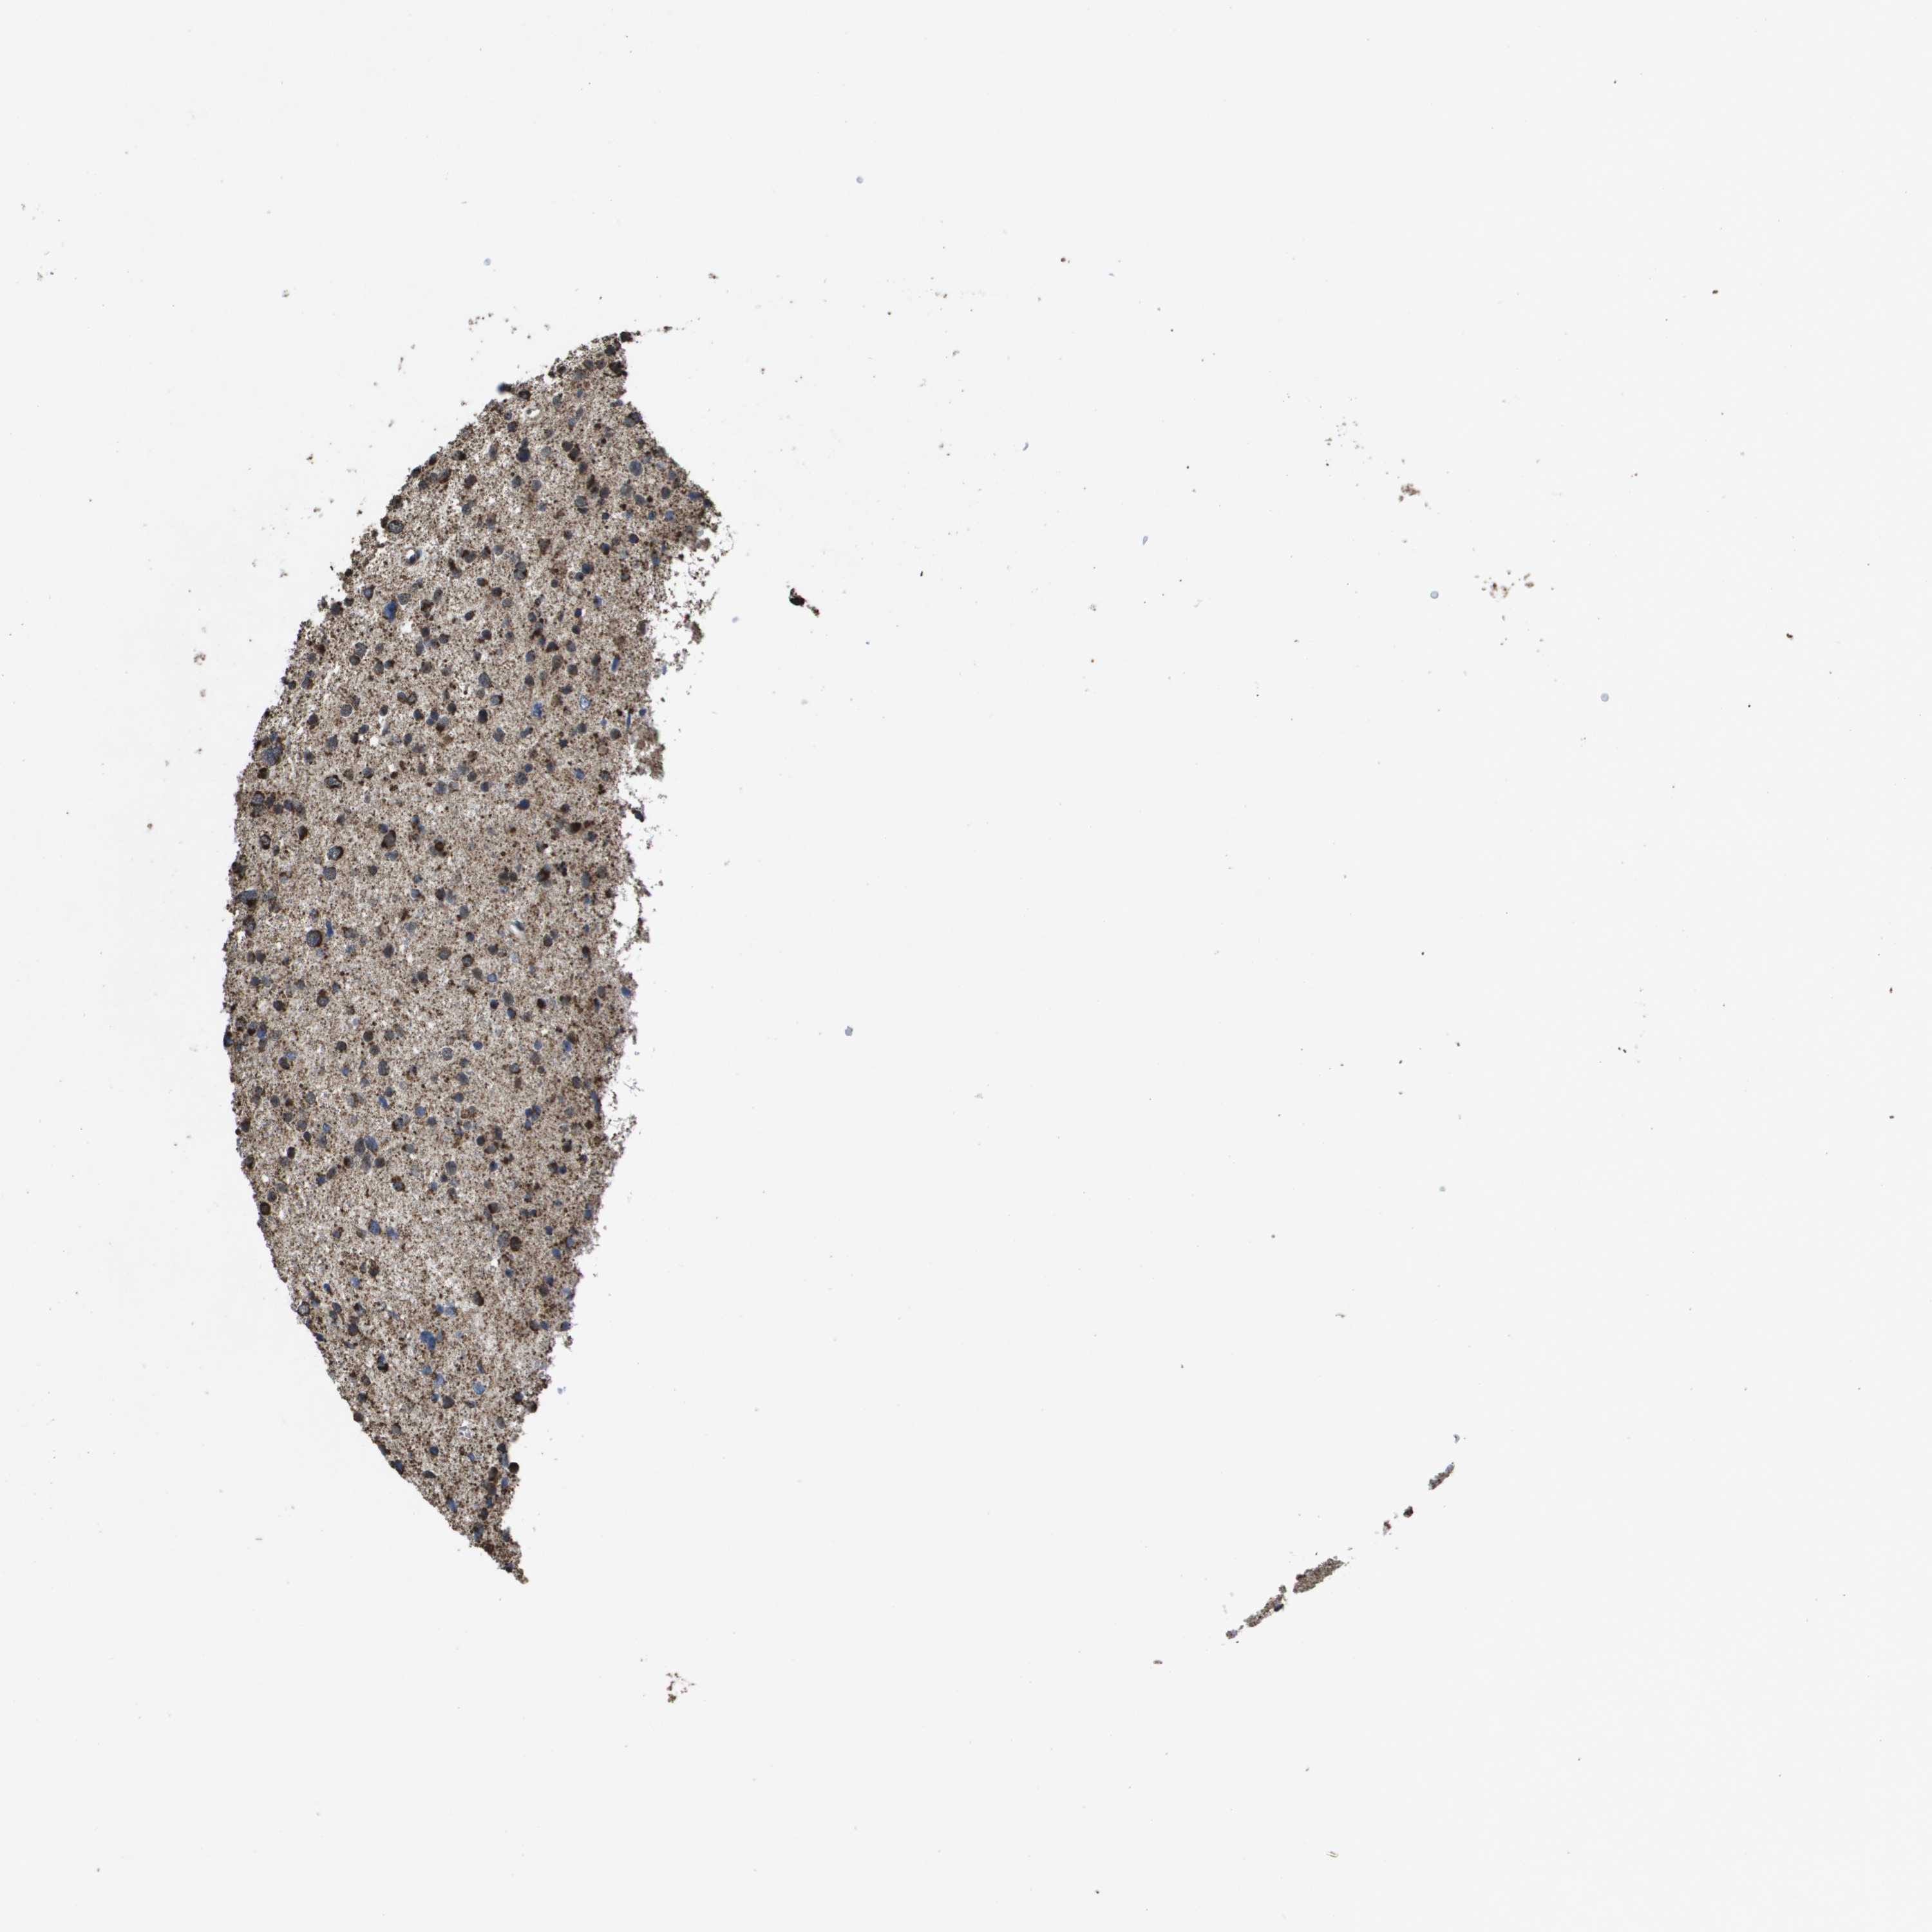

GLIOMA - Protein expressioni

A mouse-over function shows sample information and annotation data. Click on an image to view it in a full screen mode. Samples can be filtered based on level of antibody staining by selecting one or several of the following categories: high, medium, low and not detected. The assay and annotation is described here.

Note that samples used for immunohistochemistry by the Human Protein Atlas do not correspond to samples in the TCGA dataset.

Antibody stainingi

Antibody staining in the annotated cell types in the current human tissue is reported as not detected, low, medium, or high, based on conventional immunohistochemistry profiling in selected tissues. This score is based on the combination of the staining intensity and fraction of stained cells.

Each image is clickable and will lead to virtual microscopy that enables deeper exploration of all samples and also displays staining intensity scores, fraction scores and subcellular localization as well as patient and tissue information for each sample.

Antibody HPA038755

Antibody HPA048272

Antibody CAB017366

Staining

High

Medium

Low

Not detected

Intensity

Strong

Moderate

Weak

Negative

Quantity

>75%

75%-25%

<25%

None

Location

Nuclear

Cytoplasmic/membranous

Cytoplasmic/membranous,nuclear

Glioma, malignant, High grade

Glioma, malignant, Low grade

Glioblastoma, NOS